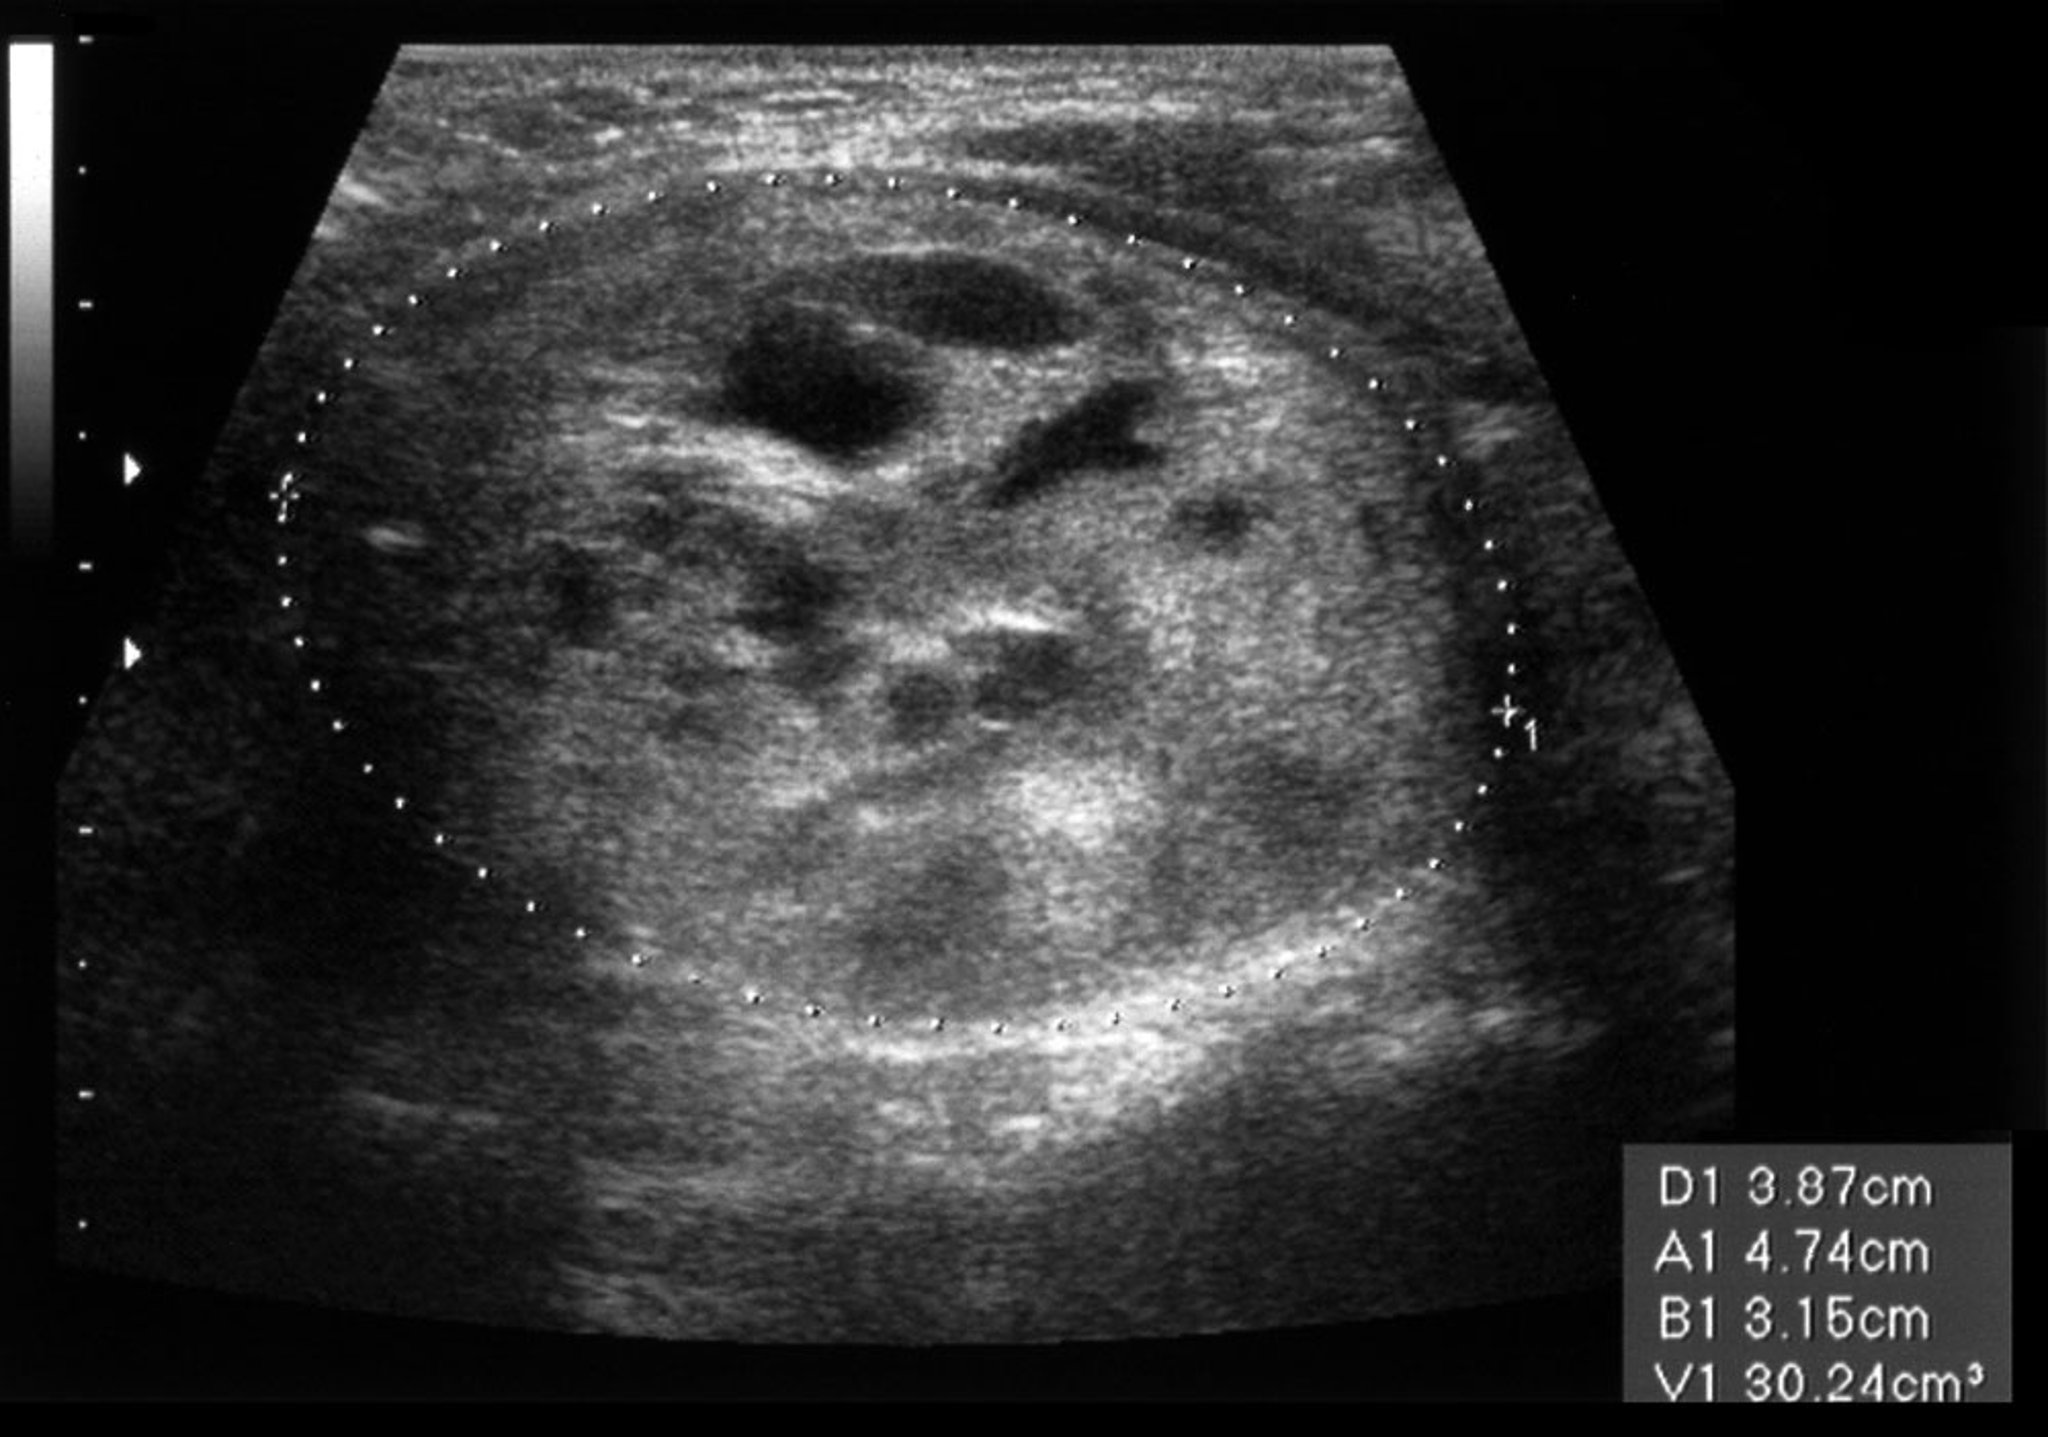

Thyroid Nodule (Ultrasound Scan)

This ultrasound scan shows a nodule in the left thyroid lobe. The nodule is 51 millimeters across on the longitudinal axis and 31 millimeters on the anteroposterior axis.

ZEPHYR/SCIENCE PHOTO LIBRARY